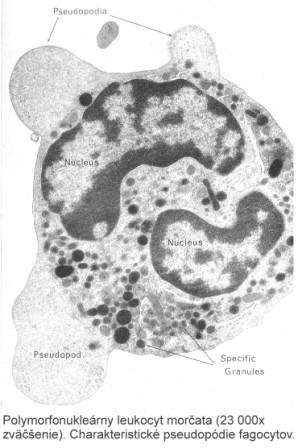

Tvar jednotlivých typov buniek je geneticky určený. Základný tvar buniek je guľovitý, z ktorého možno odvodiť všetky ostatné tvary buniek. Vznik iných tvarov buniek zapríčiňuje napríklad vzájomný tlak buniek, ktoré sú stlačené k sebe v rozličných typoch tkanív. Niektoré bunky obsahujú vnútri cytoplazmy pevné štruktúry, ktoré majú vplyv na tvar buniek (bunky svalového tkaniva obsahujú myofibrily; nervové tkanivo obsahuje neurofibrily). Aj funkcia bunky má spravidla významný vplyv na jej tvar. Biele krvinky menia svoj tvar vysielaním pseudopódií (panôžok) pri fagocytóze, alebo pri prenikaní cez endoteliálne bunky stien kapilár (diapedéza). Niektoré bunky so špecializovanou funkciou majú charakteristický tvar.